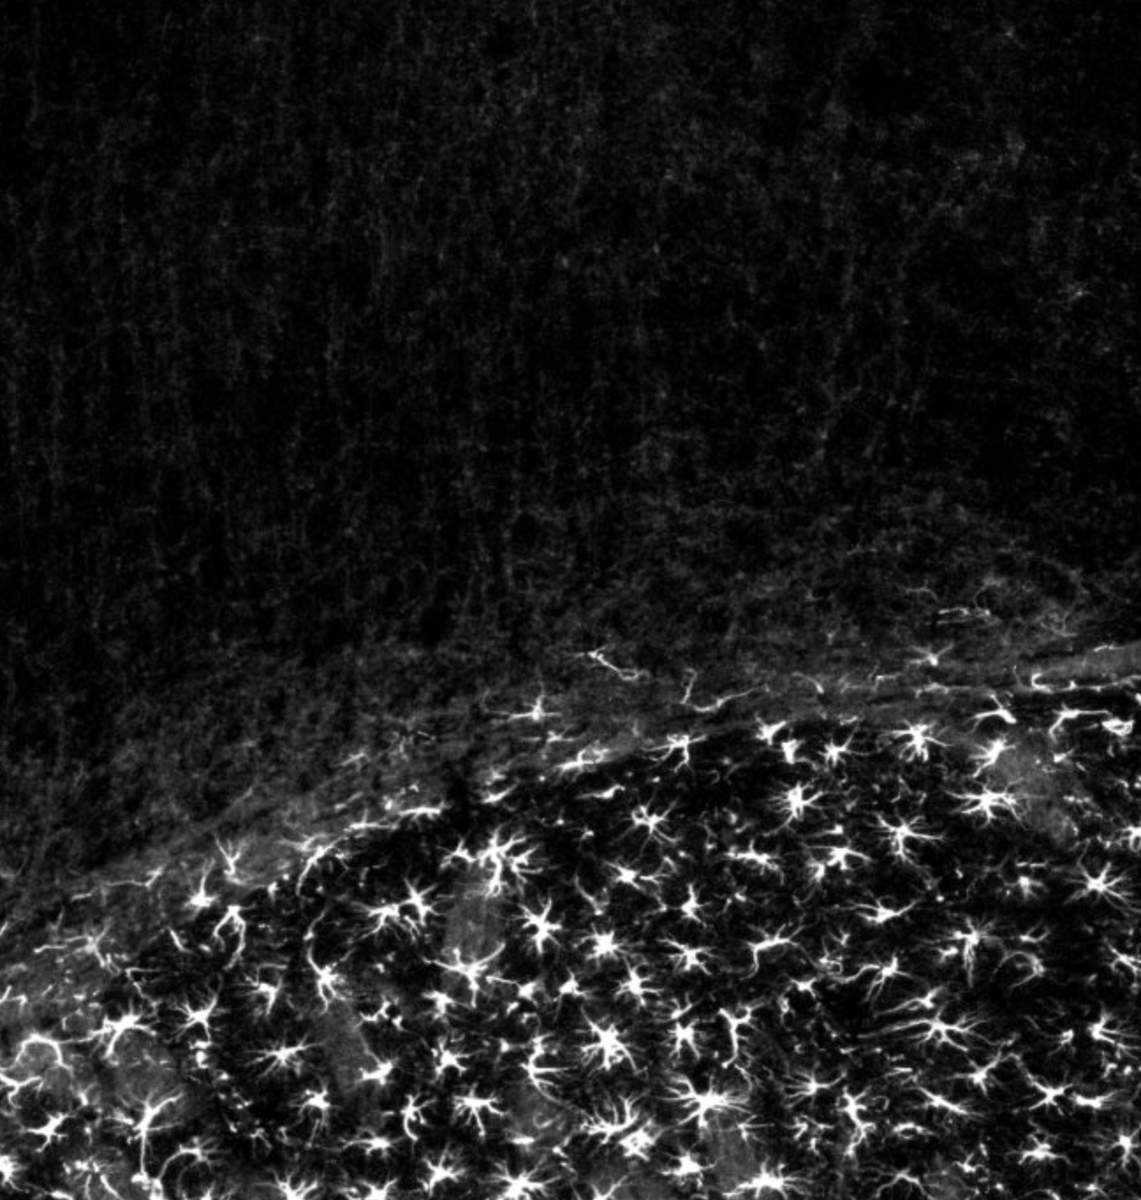

Чёрно-белый портрет астроцитов ишемии

Перед вами —  фотография активировавшихся астроцитов коры головного мозга мыши. Активация была выполнена при помощи ишемии (ограничения кровоснабжения) коры в течение 30 минут с последующей четырехдневным восстановлением. На самом деле астроциты «cветятся» зелёным, поскольку по велению авторов исследования экспрессируют зелёный флуоресцентный белок, однако для июньского конкурса Neuroart автор решил перевести снимок в черно-белый вариант. Поможет ли стандартный прием обычных фотографов — покажет голосование. Credit: Ariel Diaz/NeuroArt